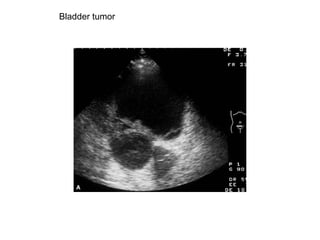

Bladder tumor

A small polypoidal tumor with a narrow base is shown.

A massive tumor involving most of the bladder is seen.